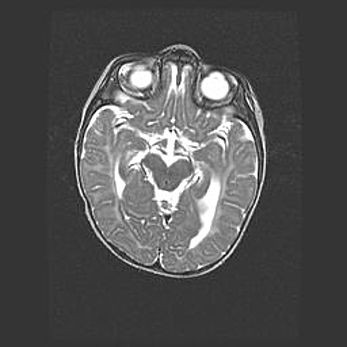

Неполная лизэнцефалия (пахигирия). Открытая гидроцефалия.

Возраст: 17 дней

Вес: 3110 г

Пол: мужской

Окружность головы: 33,5 см

Срок гестации: 35-36 недель

Лизэнцефалия—недоразвитие корковой пластинки и мозговых извилин в результате нарушения миграции нейронов коры. Поверхность мозговых полушарий гладкая. Микроскопически выявляется отсутствие нормальных слоев коры и скопление групп нейронов в подкорковом белом веществе.

Пахигирия—уменьшение числа вторичных извилин. В пораженном полушарии нервные клетки образуют толстый недифференцированный слой с неправильно расположенными нервными волокнами и группами гетеротопных клеток. Нервные клетки незрелые. Белое вещество истончено. При этом нередко аномально развит корково-спинномозговой путь.